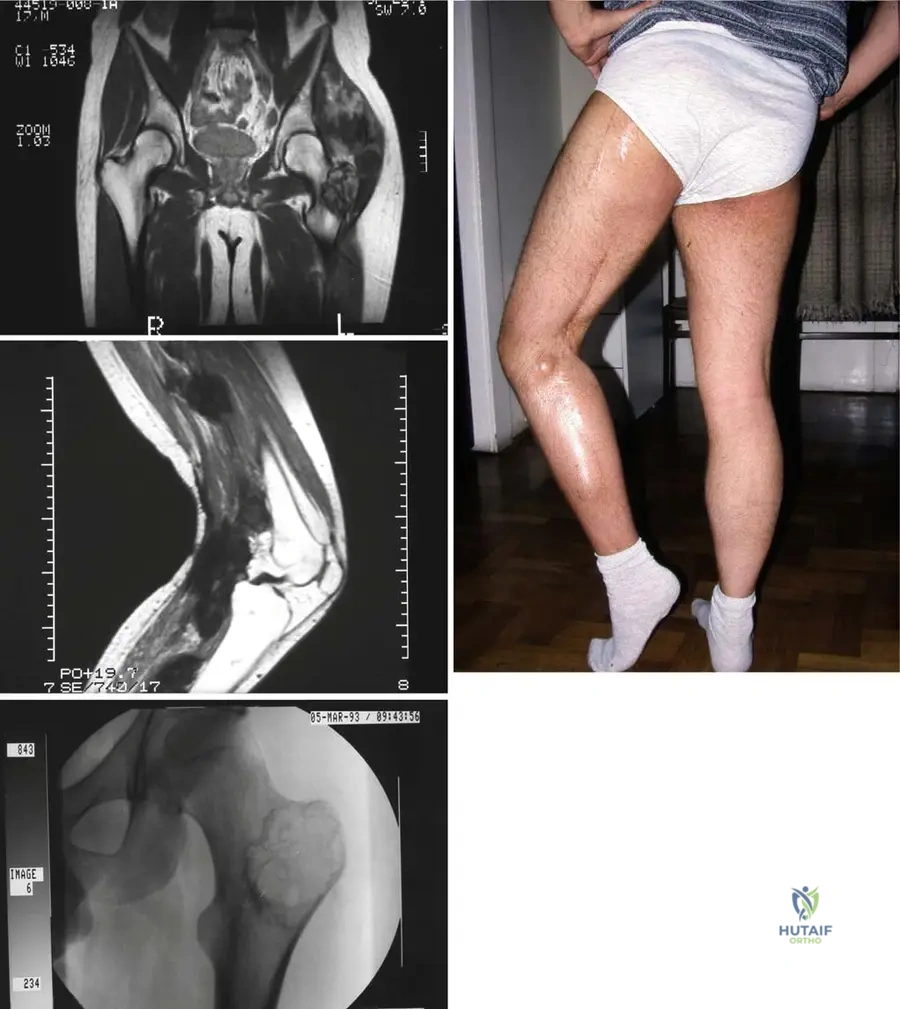

Rationale: Fig. 9.14 is described as "Subcutaneous soft tissue sarcoma fungating through the skin near the elbow." This directly matches the description of the image and the clinical presentation. Main Distractor: B) Deep intramuscular location with intact overlying skin. The image clearly shows a superficial lesion that has breached the skin, contradicting a deep intramuscular location with intact skin.

Correct Answer: A

Rationale: The clinical context for Fig. 9.15 states: "Axial T1(a) and T2-weighted image with gadolinium and fat saturation (b) showing a heterogeneous soft tissue sarcoma in the proximal forearm that is predominantly in the subcutaneous tissues abutting the adjacent myofascial plane." Main Distractor: B) Entirely within the deep muscular compartment. The image context explicitly states the lesion is "predominantly in the subcutaneous tissues," which contradicts a purely deep muscular location.